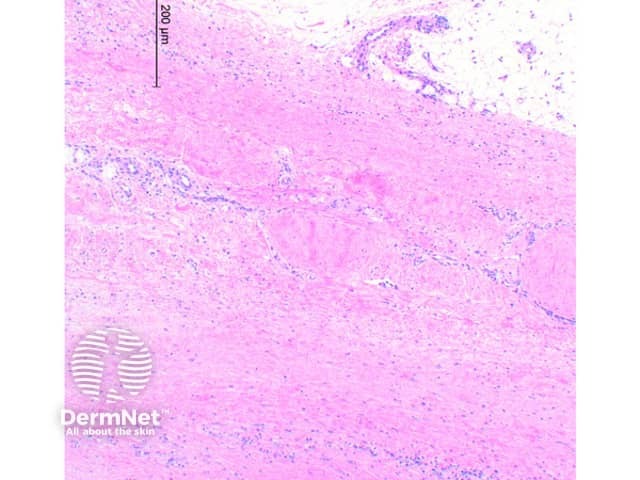

Scanning power view of eosinophilic fasciitis shows a sclerosing process affecting the deep subcutaneous tissue and fascia (Figure 1). In early disease there is oedema of the fascia and subcutaneous tissue with a lymphocytic infiltrate containing plasma cells and eosinophils. With time the collagen becomes thickened and sclerotic (Figure 2) with extension into the subcutaneous fibrous septae. Lobular involvement is rare. The tissue eosinophils may be focal around adnexal structures or diffuse within the tissue infiltrate (Figure 3). In more extensively involved cases the changes can extend to the dermis. The epidermis is typically not involved, though mild atrophy can be seen in a minority of cases.

Figure 1

Figure 2

Figure 3